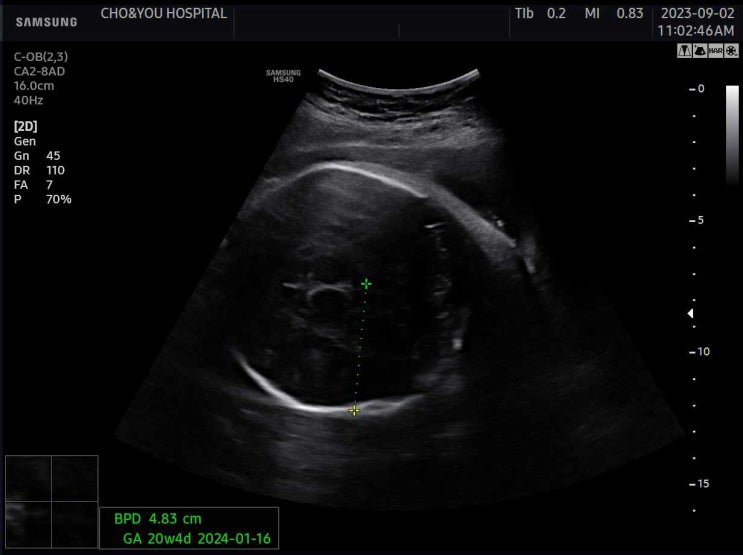

루다만남/제왕절개분만/초앤유병원

예정일이 지나도 나올기미는 없고, 아무런 소식이 없어서 병원에 방문했다. 초음파 검사를 했는데, 선생님...

임신37~39주차/태동검사

임신37주차/태동검사/내진 37주차 진입! 태동검사를 위해 방으로 들어갔다. 20분정도 소요된다고 하셨다. ...